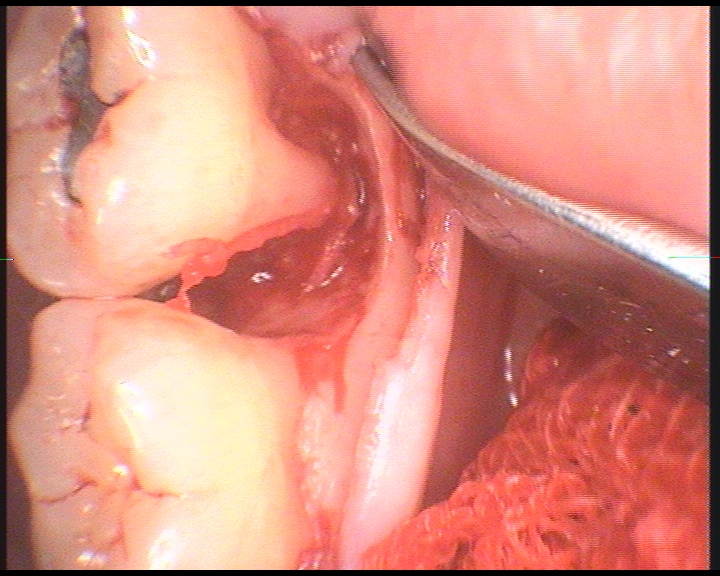

- konzervativní léčba parodontopatií včetně laseru

- chirurgická léčby parodontopatií včetně řízené tkáňové regenerace

- kompletní mukogingivální chirurgie

- plastická chirurgie parodontu

V našem stomatologickém centru se využívá pro ošetření kořenových kanálků operační mikroskop a příslušné mikroskopické techniky. Důvodem, proč používáme operační mikroskop je fakt, že dřeňová dutina, ze které vystupují kořenové kanálky bývá obvykle malá, málo přehledná a těžko ji lze běžným ordinačním světlem dostatečně osvětlit. Operační mikroskop umožňuje mnohonásobné zvětšení dřeňové dutiny i vstupy do jednotlivých kanálků. Lékař pak vidí konkrétní detail o velikosti asi jako kopací míč. Práce je pak mnohem přesnější a detailnější.

Operační mikroskop navíc přes svoji optiku svítí do dřeňové dutiny silným LED světlem, což je pro přesnost a kvalitu práce velmi důležité. Tím dosahujeme při ošetření kořenových kanálků velmi dobré a hlavně dlouhodobé úspěšnosti . Navíc nám to umožňuje ošetřovat i zuby s komplikovaným kořenovým systémem , které jsou v běžné ordinaci bez mikroskopu prakticky neošetřitelné a musí se extrahovat (vytrhnout).